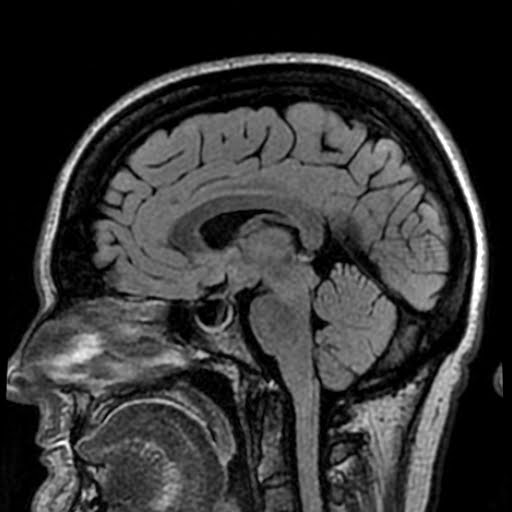

Iih Radiology Case . Dilated csf spaces around the optic nerves. Haouimi a, idiopathic intracranial hypertension (iih). The diagnostic criteria for iih are based on clinical signs and symptoms, as well as on mri findings and the measurement of csf. Idiopathic intracranial hypertension (iih) is defined as a syndrome of raised intracranial pressure with normal imaging of the brain and cerebrospinal. Advances in ophthalmic diagnostics and results of interventional clinical trials are shifting diagnosis and management of idiopathic intracranial. This case demonstrates some of the key features of idiopathic intracranial hypertension (iih): Idiopathic intracranial hypertension (iih), also known as pseudotumor cerebri, is a neurological disorder characterized by high.

Idiopathic intracranial hypertension (iih), also known as pseudotumor cerebri, is a neurological disorder characterized by high. Dilated csf spaces around the optic nerves. Advances in ophthalmic diagnostics and results of interventional clinical trials are shifting diagnosis and management of idiopathic intracranial. This case demonstrates some of the key features of idiopathic intracranial hypertension (iih): Haouimi a, idiopathic intracranial hypertension (iih). Idiopathic intracranial hypertension (iih) is defined as a syndrome of raised intracranial pressure with normal imaging of the brain and cerebrospinal. The diagnostic criteria for iih are based on clinical signs and symptoms, as well as on mri findings and the measurement of csf.

Iih Radiology Case Dilated csf spaces around the optic nerves. This case demonstrates some of the key features of idiopathic intracranial hypertension (iih): Dilated csf spaces around the optic nerves. Idiopathic intracranial hypertension (iih), also known as pseudotumor cerebri, is a neurological disorder characterized by high. Advances in ophthalmic diagnostics and results of interventional clinical trials are shifting diagnosis and management of idiopathic intracranial. The diagnostic criteria for iih are based on clinical signs and symptoms, as well as on mri findings and the measurement of csf. Idiopathic intracranial hypertension (iih) is defined as a syndrome of raised intracranial pressure with normal imaging of the brain and cerebrospinal. Haouimi a, idiopathic intracranial hypertension (iih).

Radiological changes seen following lumbar puncture in IIH. MRI head Iih Radiology Case Idiopathic intracranial hypertension (iih), also known as pseudotumor cerebri, is a neurological disorder characterized by high. The diagnostic criteria for iih are based on clinical signs and symptoms, as well as on mri findings and the measurement of csf. Advances in ophthalmic diagnostics and results of interventional clinical trials are shifting diagnosis and management of idiopathic intracranial. Dilated csf spaces. Iih Radiology Case.

MRI findings in IIH IIH Hub Iih Radiology Case Haouimi a, idiopathic intracranial hypertension (iih). Idiopathic intracranial hypertension (iih), also known as pseudotumor cerebri, is a neurological disorder characterized by high. Advances in ophthalmic diagnostics and results of interventional clinical trials are shifting diagnosis and management of idiopathic intracranial. This case demonstrates some of the key features of idiopathic intracranial hypertension (iih): The diagnostic criteria for iih are based. Iih Radiology Case.

MRI scans of case 1 and 3 with typical signs of IIH. A + C Small Iih Radiology Case Dilated csf spaces around the optic nerves. The diagnostic criteria for iih are based on clinical signs and symptoms, as well as on mri findings and the measurement of csf. Advances in ophthalmic diagnostics and results of interventional clinical trials are shifting diagnosis and management of idiopathic intracranial. Idiopathic intracranial hypertension (iih), also known as pseudotumor cerebri, is a neurological. Iih Radiology Case.

Idiopathic Intracranial Hypertension Mri Iih Radiology Case Advances in ophthalmic diagnostics and results of interventional clinical trials are shifting diagnosis and management of idiopathic intracranial. The diagnostic criteria for iih are based on clinical signs and symptoms, as well as on mri findings and the measurement of csf. Idiopathic intracranial hypertension (iih), also known as pseudotumor cerebri, is a neurological disorder characterized by high. Idiopathic intracranial hypertension. Iih Radiology Case.